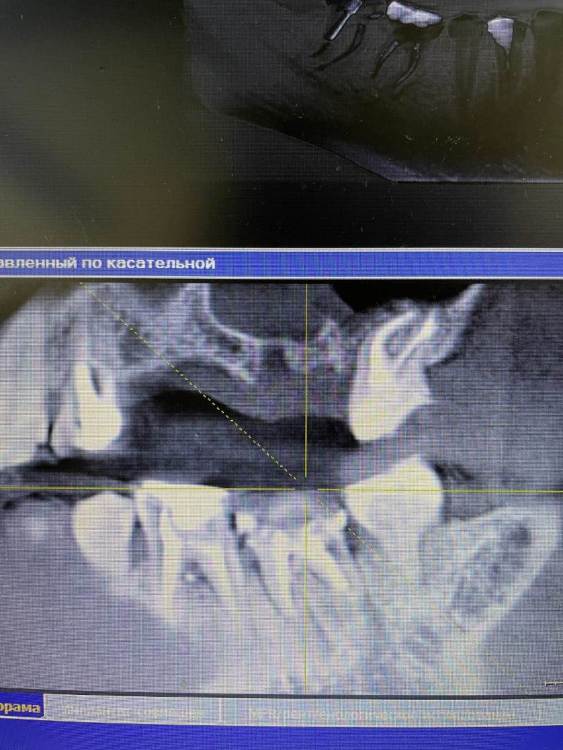

Irouil Опубликовано 21 октября, 2021 Поделиться Опубликовано 21 октября, 2021 Чтобы оценить прогноз перелеченных зубов надо увидеть ещё и снимки до лечения чтобы сравнить что было с тем, что стало. Такой вид снимка очень малоинформативен, я рекомендую либо выложить срезы из КТ интересующих Вас областей, либо выложить всю КТ 1 1 Ссылка на комментарий

Amparo743 Опубликовано 21 октября, 2021 Автор Поделиться Опубликовано 21 октября, 2021 @Irouil благодарю вас за ответ. К сожалению не знаю как извлечь из этой программы срезы или всю Кт. Мне отдали снимок на диске. И на этот снимок показывал врач и видел во всех этих зубах патологию, показывая именно с панорамы. Ссылка на комментарий

Irouil Опубликовано 21 октября, 2021 Поделиться Опубликовано 21 октября, 2021 Можете попробовать скинуть КТ в терапевтической ветке, тут надо его хорошенько посмотреть у каждого зуба чтобы оценить шансы на перелечивание, да и снимки до лечения было бы неплохо увидеть - может там динамика к улучшению стремится, но пока, судя по тем срезам что я вижу, вероятнее всего зубы действительно нужно будет удалять. Ссылка на комментарий

Bier Опубликовано 21 октября, 2021 Поделиться Опубликовано 21 октября, 2021 воспаление есть, скорее всего хирург прав, еще одно перелечивание они не перенесут. Ссылка на комментарий